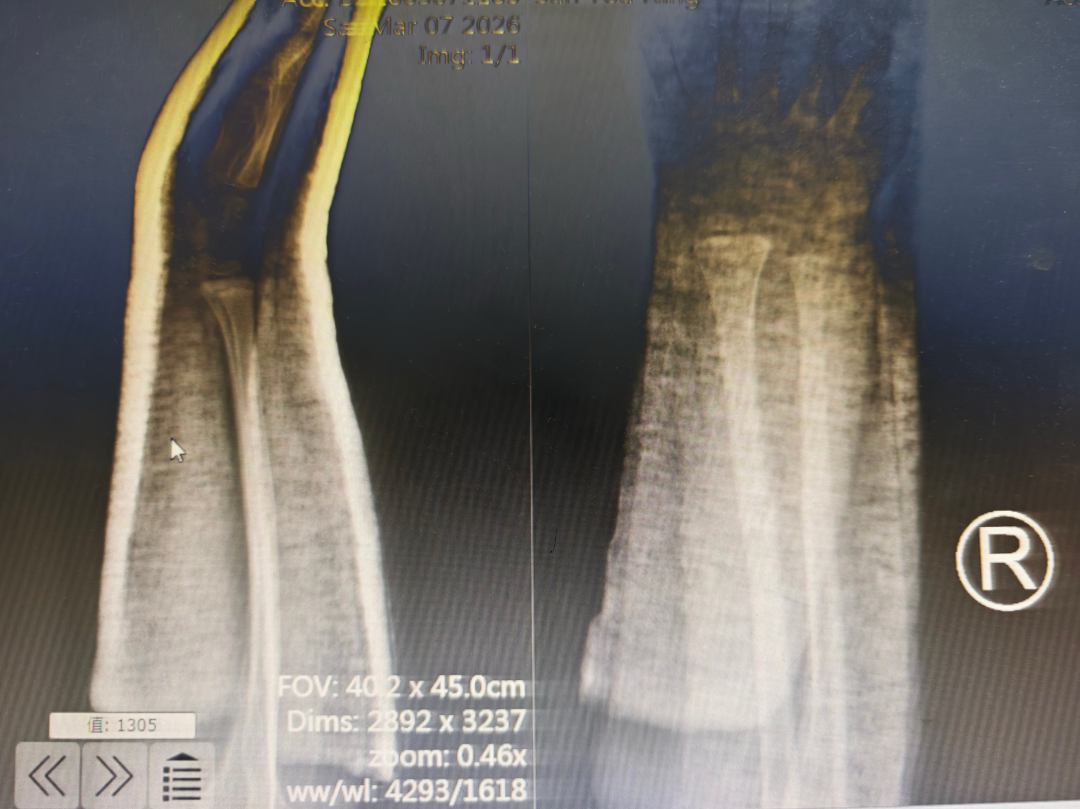

这名小患者是在玩耍时不小心摔伤的,右前臂当即出现肿痛、变形,家人赶紧把他送到了医院。接诊的杜龙龙主治医师仔细检查后,确诊为右前臂桡尺骨双骨折,而且断端错位很明显。考虑到孩子正处于生长发育的关键阶段,杜医生解释,如果这种骨折处理不好,很可能会影响到他未来的骨骼发育和手臂功能。

在董博主任医师、周健副主任医师的精准指导下,杜龙龙主治医师凭借娴熟的技术,在X光透视辅助下,精准把控力度与方向,轻柔而稳健地完成牵引、复位等一系列操作。整个过程创伤为零,痛苦降至最低。复位后影像复查显示:骨折端对位对线良好,畸形消失,复位成功!